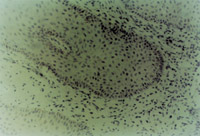

原位切取創(chuàng)面組織病理切片檢查,見壞死上皮組織間有大量顆粒樣組織,新生上皮細(xì)胞和膠原纖維組織呈團(tuán)樣增生,并可見到典型的類似于胎兒皮膚結(jié)構(gòu)的皮膚胚胎基(embryonic base,EB)(圖5-3-4a,5-3-4b)。MEBT治療10天后,在創(chuàng)面邊緣取上皮組織病理切片可見到較原始的上皮組織。

5-3-4a 新生上皮組織和膠原纖維增生,可見典型EB(皮膚胚胎基) HE×40

5-3-4b 新生上皮組織中可見微血管,膠原纖維和上皮細(xì)胞(干細(xì)胞)形成的皮膚胚胎基組織  HE×40